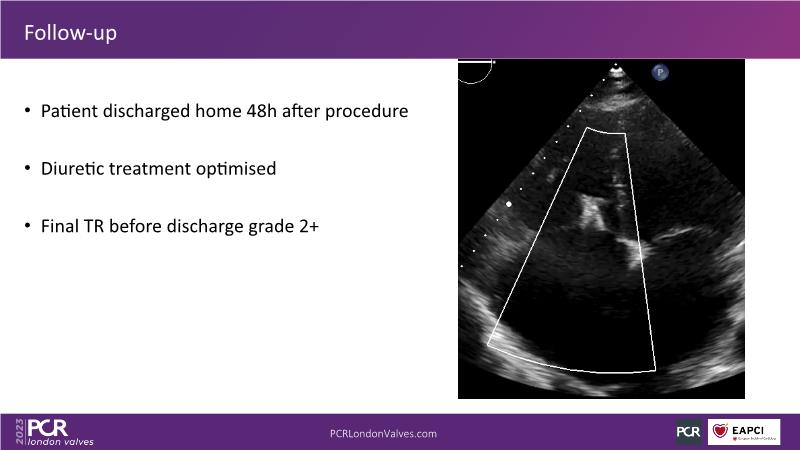

This session offers an opportunity to engage in a real case discussion led by an advanced Heart Team. Participate in discussions on controversial decision-making scenarios and stay informed about the latest clinical evidence related to MitraClip, Tendyne, and TriClip therapies.